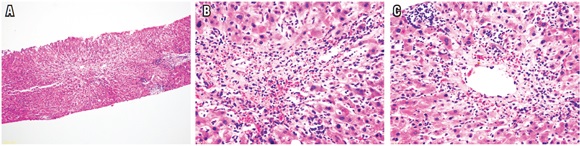

- Inflamación portal: cualquier grado de inflamación portal con presencia de una población heterogénea de células inflamatorias, tales como linfocitos T activados, inmunoblastos y eosinófilos, acompañados de algunos plasmocitos y polimorfonucleares neutrófilos. Puede existir leve o mínima inflamación lobulillar, en parches (Figura 5)

- Lesión inflamatoria de la vía biliar: ductulitis o presencia de células inflamatorias linfoides en el epitelio de ductos pequeños (<30 µm) y cambios degenerativos dados por aumento de la relación núcleo/citoplasma, hipercromasia y pleomorfismo nuclear, seudoestratificación nuclear o alteración de la polaridad, mitosis, vacuolización paranuclear del epitelio ductal; puede existir ruptura de la membrana basal (Figura 6).

- Inflamación vascular endotelial: no está presente en todos los casos, se localiza a nivel portal y/o en la vena hepática terminal o central, con inflamación subendotelial de linfocitos, prominencia y desprendimiento endotelial. Endotelialitis sinusoidal muy ocasionalmente puede estar presente (Figura 7).

Se observa hasta en el 30% de los casos, también es más frecuente en el rechazo agudo tardío (después del día 100) y en rechazos pediátricos. Se caracteriza por la endotelitis o inflamación de las vénulas terminales; a veces acompañado de congestión, extravasación de hematíes y dilatación sinusoidal, con leve o mínima inflamación, hepatocitos apoptóticos aislados en su vecindad (zona 3) (Figura 8). A diferencia del rechazo agudo celular clásico, el endotelio usualmente no presenta cambios de endotelialitis; en la mayoría de los casos aparece esencialmente normal. Puede acompañarse de rechazo agudo celular con cambios inflamatorios a nivel portal o presentarse como venulitis central aislada (27,28).

En ocasiones la inflamación del lobulillo o hepatitis lobulillar domina el cuadro morfológico, con mínimos cambios a nivel portal o presencia de cambios inespecíficos. Se observa especialmente en niños; también se ha descrito en los adultos que suspenden abruptamente inmunosupresión después de estar recibiéndola plenamente. El lobulillo muestra infiltrado de linfocitos (hepatitis linfocítica) leve o en parches, con algunos cuerpos apoptóticos dispersos y células de Kupffer hiperplásicas, mínima inflamación portal, con leve ductulitis, sin evidencia de inflamación endotelial, ni tampoco compromiso de venas centrales (Figura 9). El principal diagnóstico diferencial es la recurrencia temprana de hepatitis C, infección por virus de Epstein-Barr (VEB) y toxicidad medicamentosa (26).